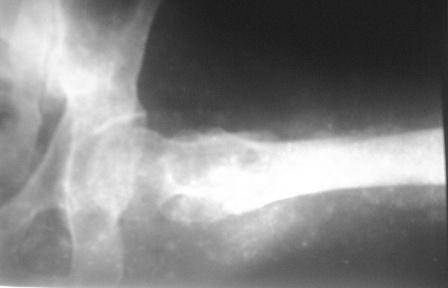

Больному 50л. В отдаленном от центра р-не ДТП 6.12.08г. д-з " тяжелая ЧМТ, мн.перломы ребер слева,отрыв ножки селезенки, повреждение п/ж железы, з/двойной перелом прав.бедра.

После экстрен. хирургических вмешательств, конечность фиксирована кокситной гипсовой лонгетной повязкой. Кома 2 нед, нагноение п/о раны живота, посттравмат. пневмония. 20.01.09г. переведен к нам. Постельный больной, ослабленный,бледный, весом 56кг: свищ п/о раны перед. брюшной стенки с сукровичным выделением, гипс снят - деформация и укорочение бедра на 6 см, в обл перелома есть спайка. слабо, но активно поднимает ногу, контрактура т/б и коленных суставов. Обшеукреп. лечение, компоненты крови, общ. массаж, ЛФК и больной активизирован, начал ходить с костылями, движения в суставах почти восстановлены. НВ-112, эр-3,5млн. Наш план блокир. и/м остеосинтез. Имеется гвозди для ВНПБ ЦИТО, но PFN не имеется